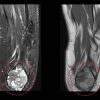

The patient was discharged with instructions for daily wound care, suture removal in 15 days, and immobilization until further medical guidance. At the first post-operative follow-up, 1 month later, the patient was asymptomatic, with a well-healed surgical wound and no signs of infection. Shoulder abduction was limited to 40°, with reduced muscle strength and restricted internal and external rotation. Histopathological analysis confirmed the diagnosis of chondroblastoma with aneurysmal changes. Currently, at the 6-month follow-up, the patient remained asymptomatic, with a healed surgical site. However, joint mobility and strength were still limited to 60°, and the patient continue with physical rehabilitation (Fig. 5).